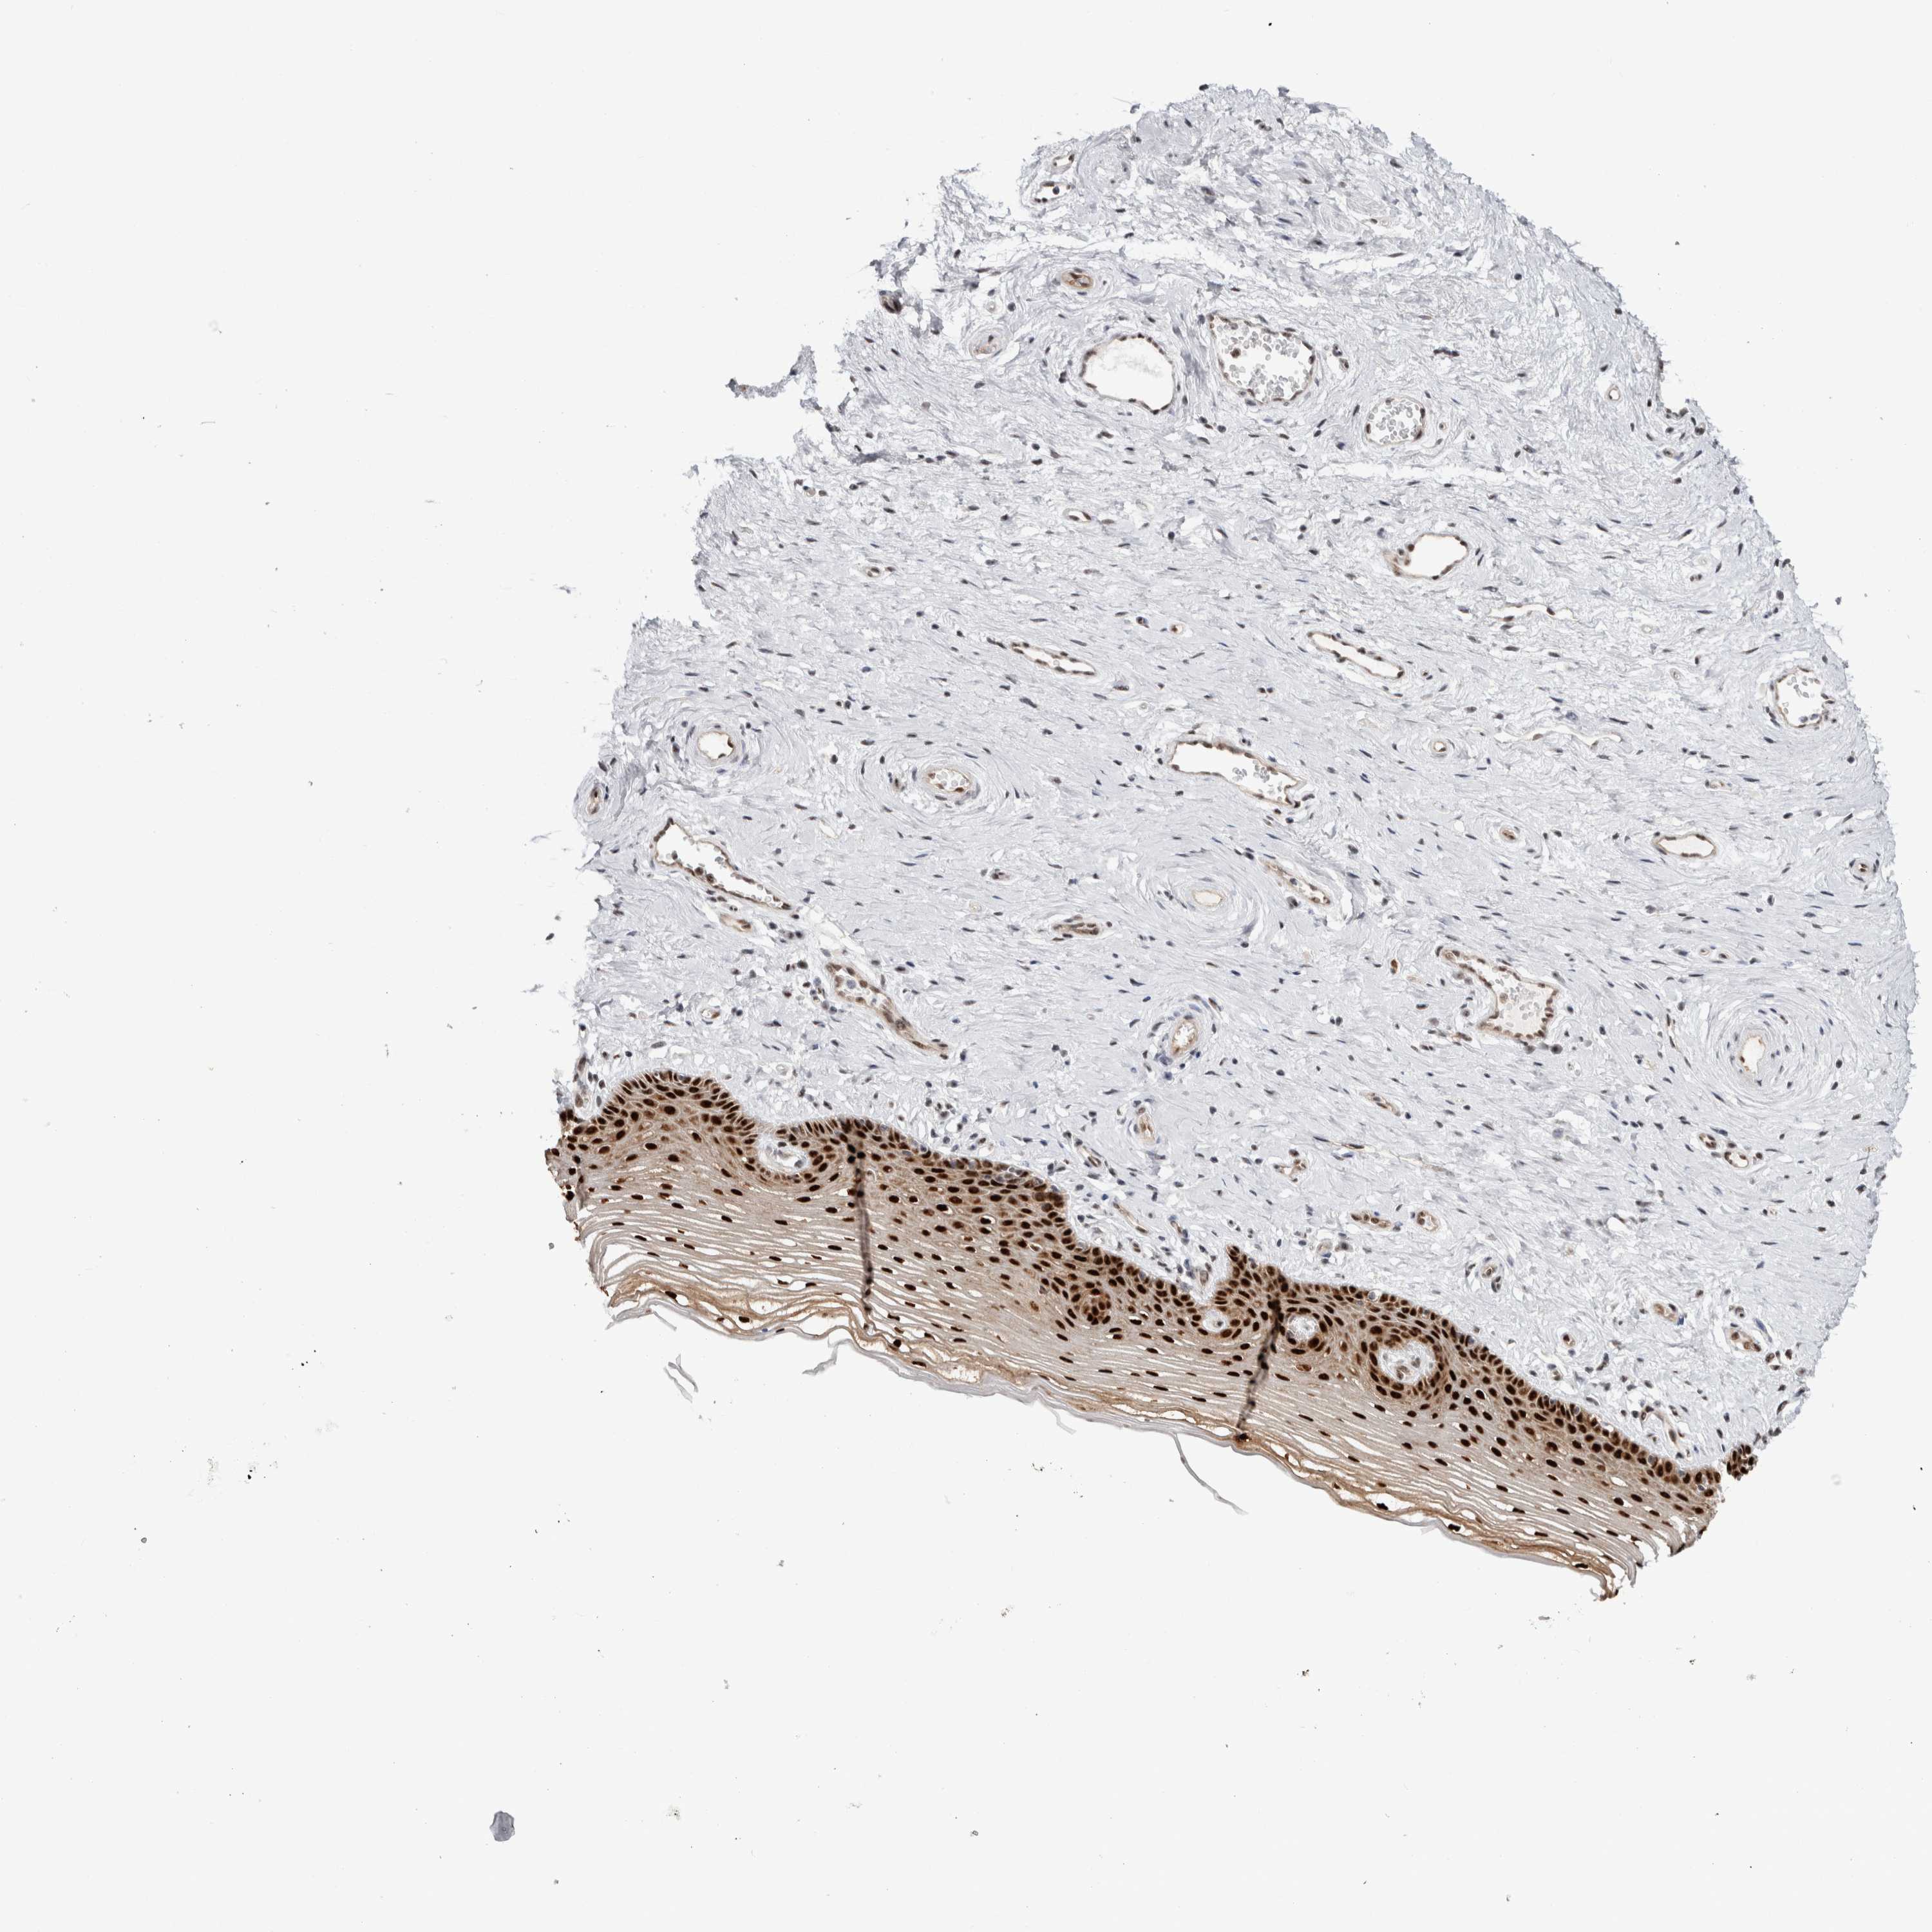

VAGINA - Antibody stainingi

Antibody staining in the annotated cell types in the current human tissue is reported as not detected, low, medium, or high, based on conventional immunohistochemistry profiling in selected tissues. This score is based on the combination of the staining intensity and fraction of stained cells.

Each image is clickable and will lead to virtual microscopy that enables deeper exploration of all samples and also displays staining intensity scores, fraction scores and subcellular localization as well as patient and tissue information for each sample.

Antibody CAB027355Antibody CAB037310

Squamous epithelial cells HighMedium